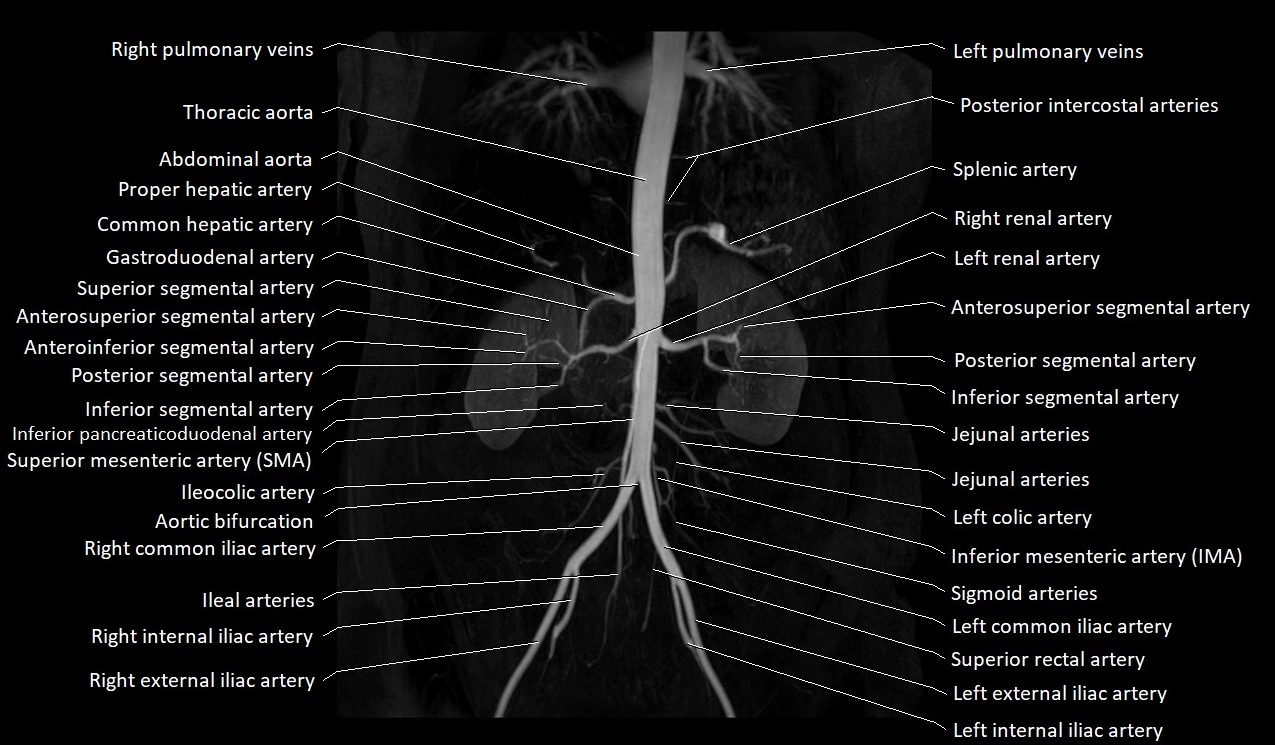

CT images

image